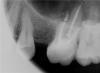

Доктор Саша Опубликовано 20 июня, 2011 Поделиться Опубликовано 20 июня, 2011 (изменено) http://s11.radikal.ru/i184/1106/de/7dda12ed9aeb.jpg Вы бы перелечили? Изменено 20 июня, 2011 пользователем Доктор Саша Ссылка на комментарий

Kivilgar Опубликовано 20 июня, 2011 Поделиться Опубликовано 20 июня, 2011 http://s11.radikal.ru/i184/1106/de/7dda12ed9aeb.jpgВы бы перелечили?http://s57.radikal.ru/i155/1106/f0/ea6d20dcaaa8.jpg По мне так серьезный косяк ничего хорошего не ожидается. А кто это так умудрился? Ссылка на комментарий

Доктор Саша Опубликовано 20 июня, 2011 Автор Поделиться Опубликовано 20 июня, 2011 http://s57.radikal.ru/i155/1106/f0/ea6d20dcaaa8.jpg По мне так серьезный косяк ничего хорошего не ожидается. А кто это так умудрился?латералка..все померил..по локатору.но - видимо протолкнул... Ссылка на комментарий

Доктор Саша Опубликовано 20 июня, 2011 Автор Поделиться Опубликовано 20 июня, 2011 латералка..все померил..по локатору.но - видимо протолкнул... мляяяя....главное 4 канал тоже... Ссылка на комментарий

Доктор Саша Опубликовано 20 июня, 2011 Автор Поделиться Опубликовано 20 июня, 2011 (изменено) Поясню....делал конусной гуттой...мту на моторе...неправильно(видимо) промерил мед каналы по апекс локатору..рентгена сразу в кабинете нет...сказал что может быть перелечу..(все мля покупаю RVG) конусность 04 + 02 доконденсировал...Но....Есть 3 недели чтобы принять решение о переделке..Может бывалые в этом форуме все таки ответят уже?...или только критиковать? могу еще снимки сделать... Изменено 20 июня, 2011 пользователем Доктор Саша Ссылка на комментарий

Доктор Саша Опубликовано 22 июня, 2011 Автор Поделиться Опубликовано 22 июня, 2011 Гутта не деформирована,большои номер,силлер подкиснет метазон и подавно вымоется герметизма то нет.ИМХО можно попытаться на свои страх и риск вкрутить H фаил и потихонечку вытащить.При условии если латералка была конуснои гуттои(не метовская) 25-30 номера гутта конусная 04(VDW), размер 35. Силер AH plus, обработка мотором..Либо я верхушку раздолбил так, либо что то еще Ссылка на комментарий